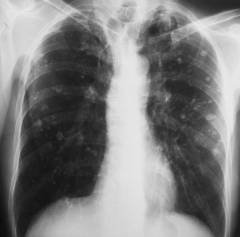

Кавернозный туберкулез легких. Основной признак – очаговое затемнение с четким просветлением в центре.

В правом легочном поле ближе к периферии – каверна округлой формы. Прослеживается дорожка к корню. Второй снимок демонстрирует обострение процесса через несколько месяцев.